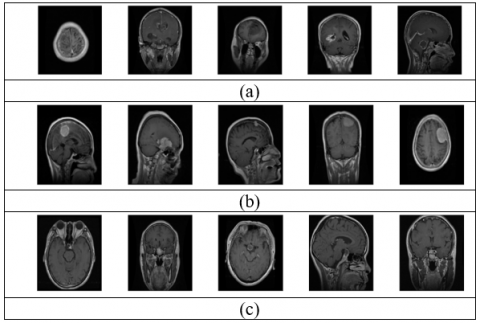

The T1-weighted MRI brain tumor dataset is publicly available for research community at https://figshare.com/articles/brain_tumor_dataset/151242. This image data was initially used by Cheng. et al. in 2017 [12] for tumor type classification. The MRI image dataset contains 2-D images of three brain tumor types (1. menigioma, 2. glioma, and 3. Pituitary). In addition, the database consists three plane views (i.e. axial view, coronal view, and sagittal view) of three types of brain tumors, which are shown in the Figure 1). As shown in the Table 1, the dataset contains 3064 MRI images from 233 patients over all three views and three tumor types. The dimensions of each MRI image are 512x512 pixels. All the statistical details of the MRI image dataset are given in the Table 1.

Figure 1. The various types of tumors in different plane views

Figure 2. Uncropped images for tumor (a) meningioma (b) glioma (c) pituitary